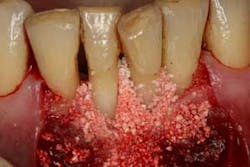

Figures 7a, 7b, and 7c: Osseous surgery in the mandibular anterior sextant with debridement of root surfaces and then regeneration.

Briefly, during osseous surgery, the upper right molars were treated with a combination of autograft and platelet-derived growth factor/Beta-tricalcium phosphate along with a porcine collagen graft (figures 5a and 5b). The upper left osseous surgery consisted of the same treatment (figures 6a and 6b), but also included the extraction of a hopeless tooth No. 15. Once again, the anterior osseous surgery consisted of the same regenerative materials as the former surgeries but with the addition of a porcine soft-tissue graft (figures 7a, 7b, and 7c). After the initial healing phase, the patient was placed on a strict home-care regimen and was seen every eight to 12 weeks for hygiene recare. The patient maintained excellent hygiene throughout the five-year follow-up period.